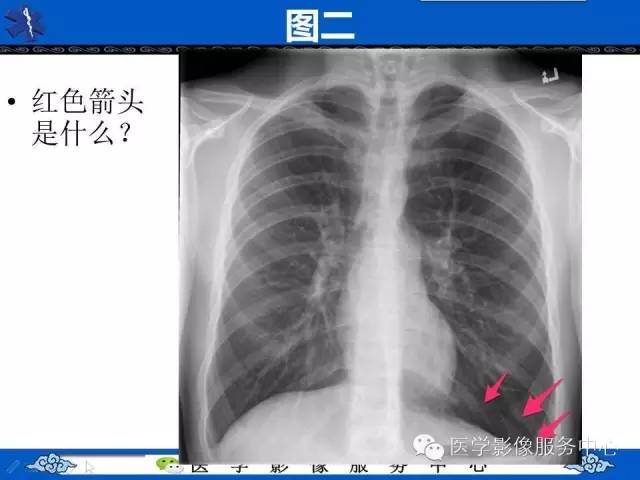

【影像征象】深沟征——气胸间接征象